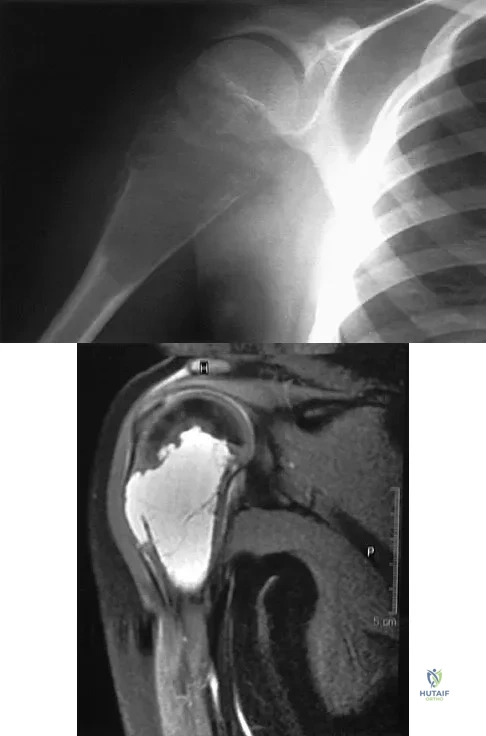

A 36-year-old woman has pain and swelling of the anterior arm after undergoing arthroscopic shoulder surgery 8 months ago. At the time of the procedure, extensive debridement and synovectomy of the anterior aspect of the joint was performed to remove scar tissue that had formed after an open rotator cuff repair. Examination reveals a golf ball-sized swelling just lateral to the coracoid. The area is not warm and shows no other signs of infection. An MRI scan is shown in Figure 1. Management should now consist of

Explanation